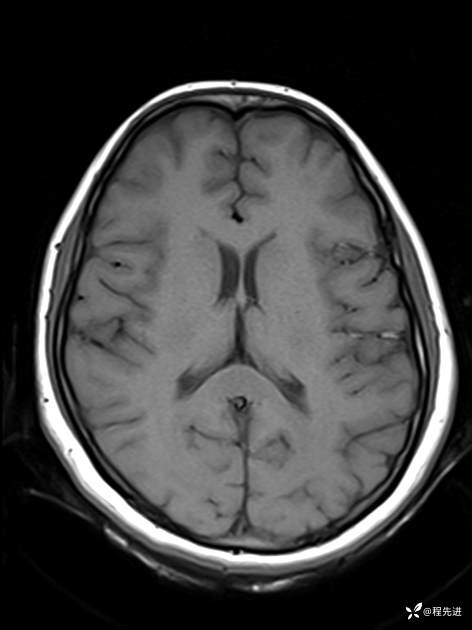

【患者信息】:女,25岁

【现病史及既往史】:言语含糊、意识状态改变1天。有下段剖宫产术10天病史。